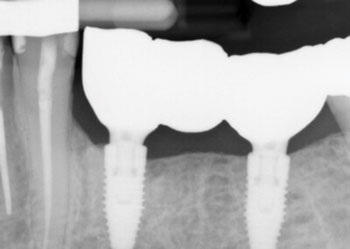

The following radiographs demonstrate representative surgical cases treated with a laser-assisted protocol, illustrating resolution of peri-implant radiolucency, stabilization of crestal bone levels and improved bone density patterns over time.

Fig. 3 shows a dental implant at site #21 functioning as the mesial abutment of a three-unit implant-supported fixed partial denture, which initially presented with a distal vertical osseous defect. At nine months postoperatively, radiographic evaluation demonstrates osseous fill on the distal aspect, along with increased radiographic bone density on the mesial aspect.

Fig. 3: Initial and follow-up radiographs of dental implant at site #21.